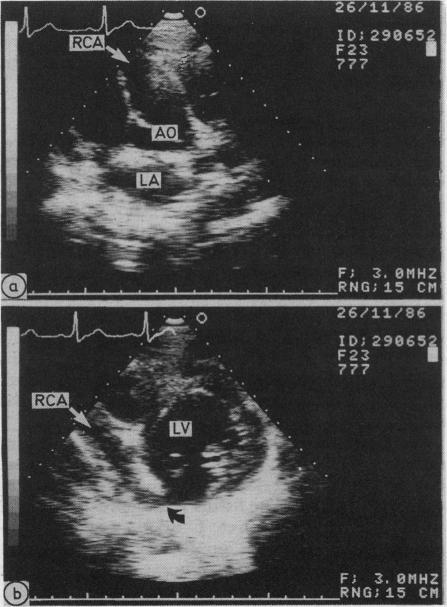

A case of right coronary to left ventricular fistula was diagnosed by cross sectional and Doppler echocardiography. The origin and site of entry into the left ventricle of the enlarged right coronary artery were shown by cross sectional echocardiography. Diastolic flow was detected in the left ventricle by both pulsed and continuous Doppler echocardiography. The fistula was confirmed by cardiac catheterisation and was successfully closed at operation.

一例右冠状动脉至左心室瘘通过断层扫描和多普勒超声心动图得以诊断。断层扫描超声心动图显示了增粗的右冠状动脉的起源及进入左心室的部位。脉冲式和连续性多普勒超声心动图均检测到左心室内的舒张期血流。经心导管检查证实存在瘘管,并在手术中成功闭合。